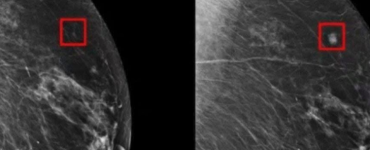

Salute e Benessere Una nuova intelligenza artificiale può rilevare il tumore al seno fino a 5 anni prima della diagnosi Emanuela B.02/05/2025